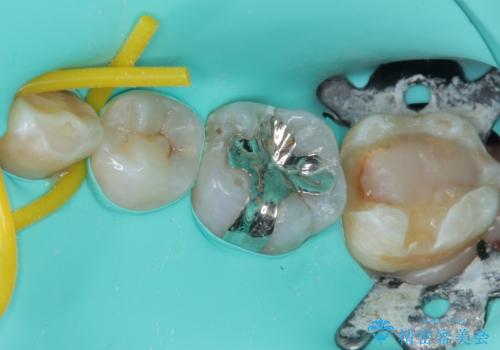

拡大鏡視野下で、保険のプラスチック、虫歯の除去を行い、セラミックインレーに適した形に整えました。

歯と歯茎の間に圧排糸と言われる糸を入れてシリコーン印象材にて精密な型どりをしました。

セラミックインレーの装着時には、唾液の侵入を防ぐために、ラバーダム防湿を行いました。